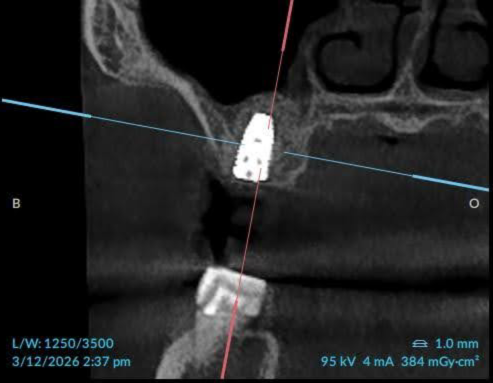

After